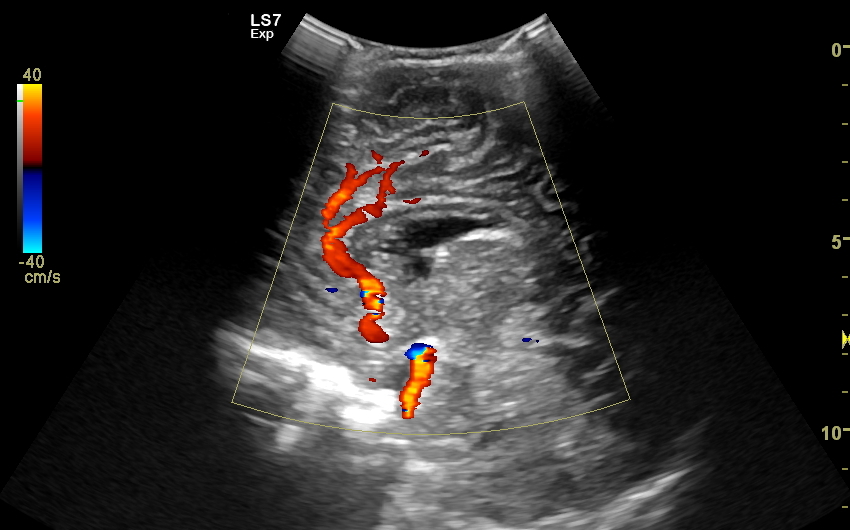

W USG główki dziecka oceniane są struktury wewnątrzczaszkowe, tj. mózg wraz z jego układem komór wewnętrznych, sploty naczyniówkowe, istota biała mózgu i obszary jąder podstawy mózgu, morfologia zakrętów i bruzd mózgowia, przestrzeń przymózgowa, a w trybach dopplerowskich wybrane naczynia tętnicze i żylne mózgu, w tym zatoki żylne. Oceniane są również cechy ciśnienia śródczaszkowego. W opisie badania podawane są również wymagane przez neurologa tzw. wskaźniki komorowe oraz wymiary wybranych struktur.